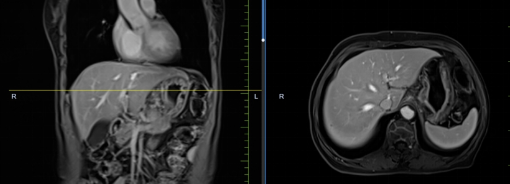

患者孟某某,女,73歲,因腹部不適行胃鏡及PET-CT,發(fā)現(xiàn)胃癌、骨、肺、肝多發(fā)轉(zhuǎn)移,胃壁厚約2cm,腹腔大淋巴結(jié)約3cm,肝最大轉(zhuǎn)移灶約3cm。同樣6周期化療+免疫,聯(lián)合中醫(yī)中藥后病灶明顯縮小,現(xiàn)已進(jìn)入維持治療階段,身體狀況恢復(fù)至常人水平。

治療前

治療后